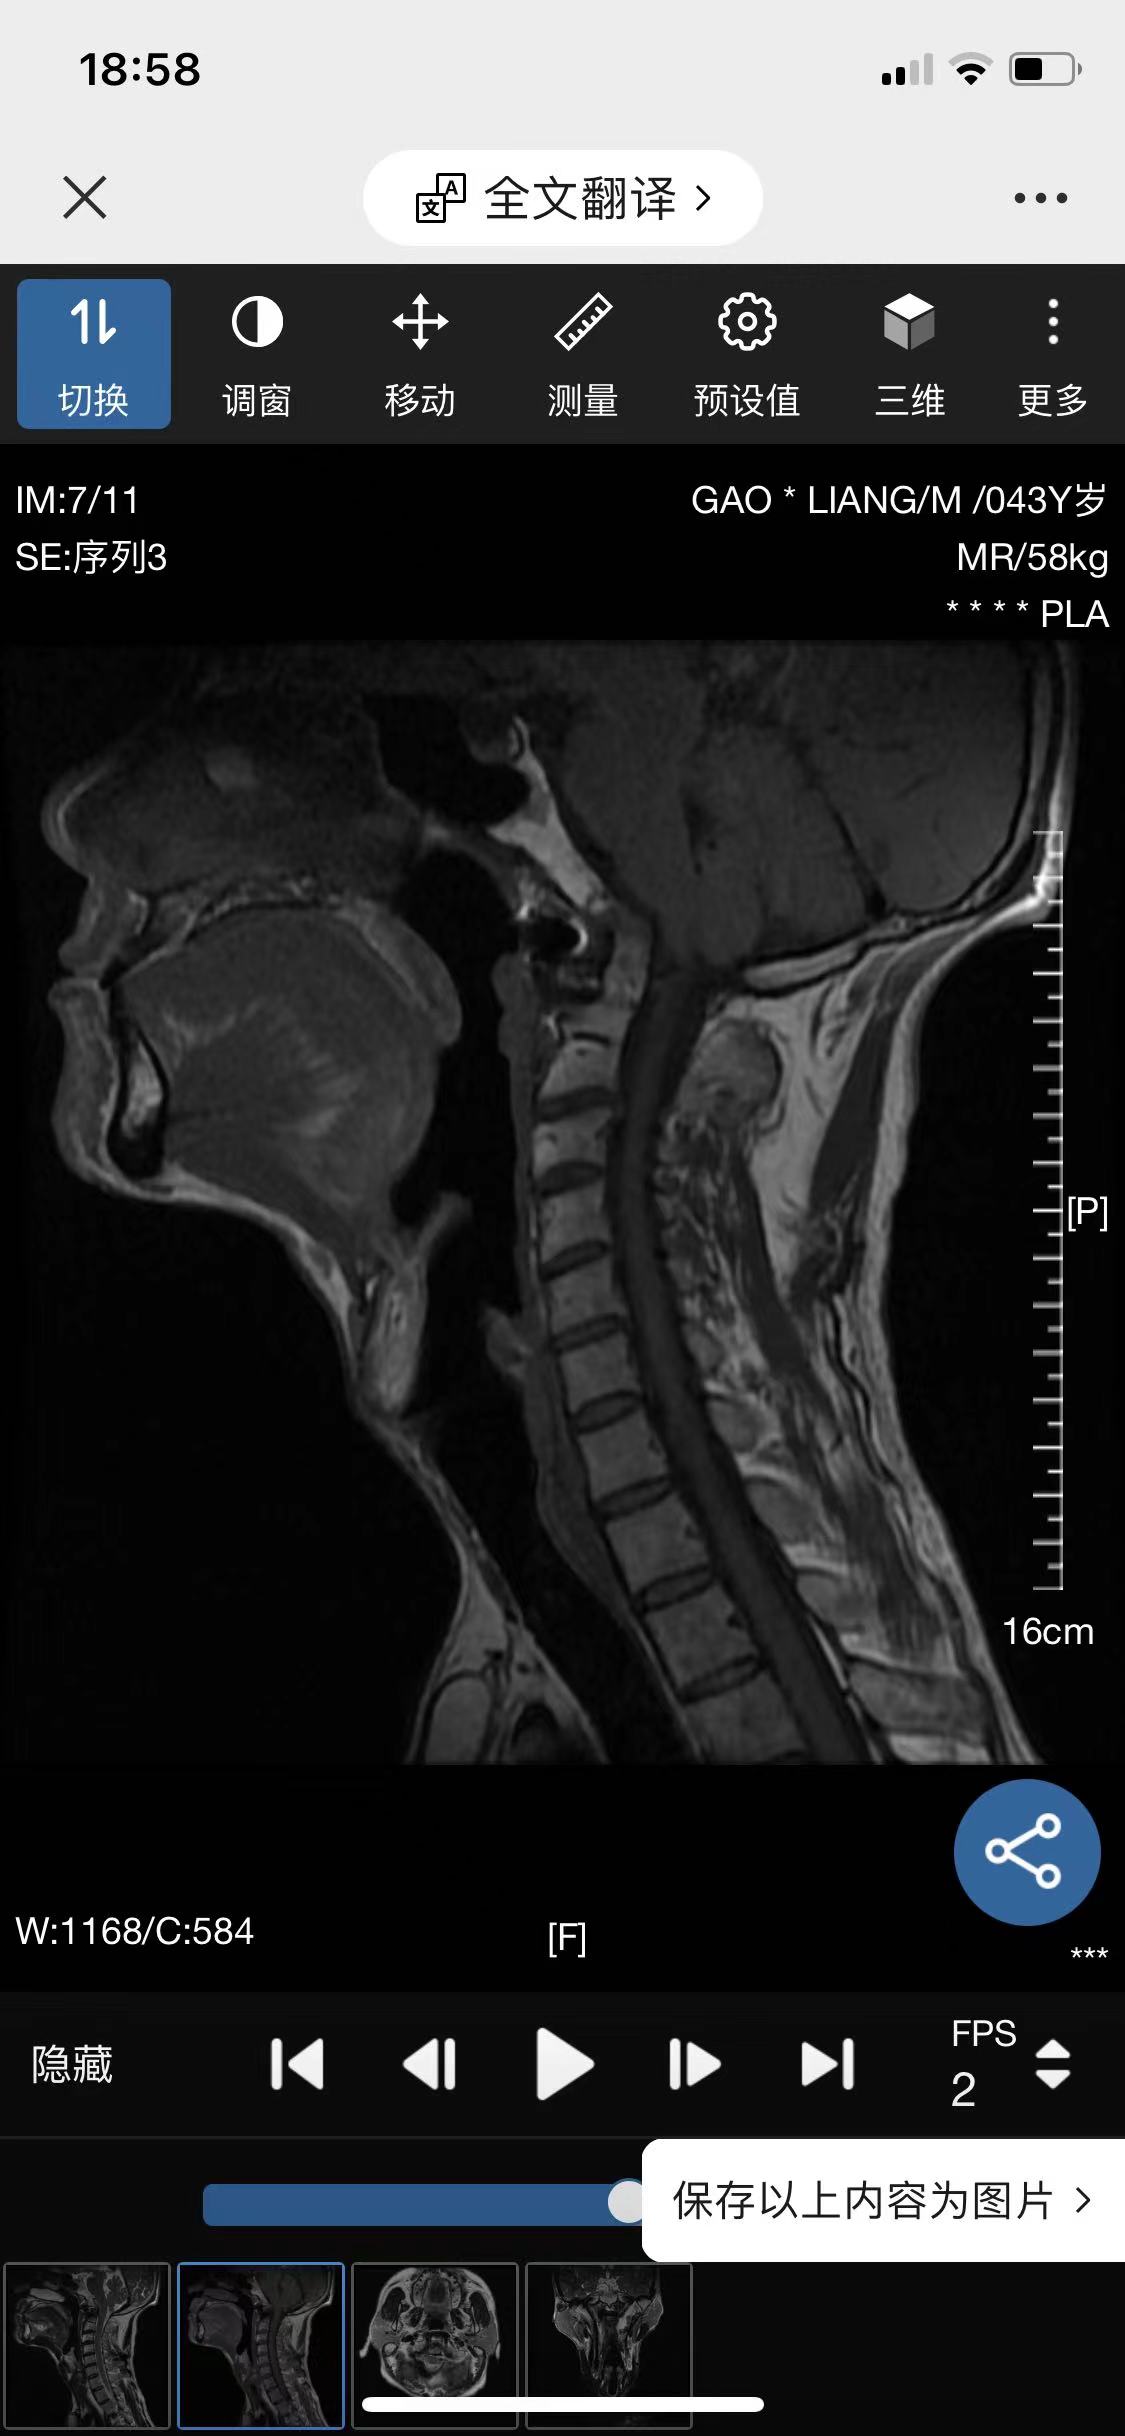

• 诊断:寰枢椎脱位

• 影像:

• 术后影像: